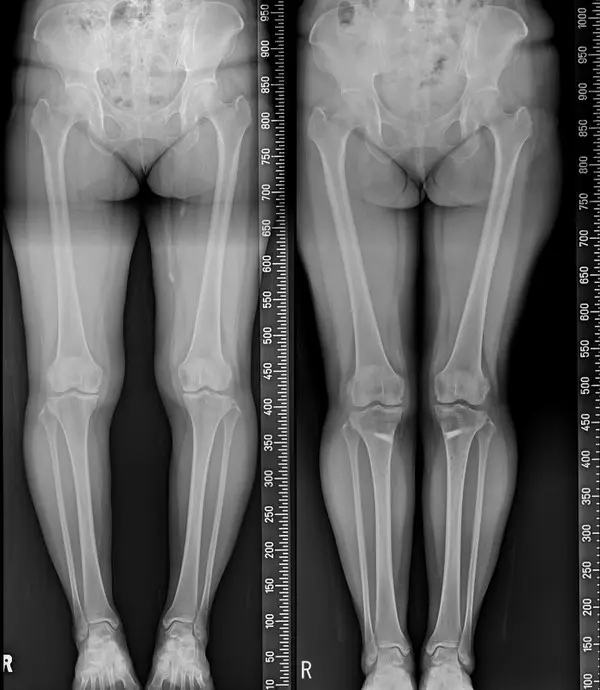

휜다리는 무릎의 건강상태와 걸음걸이, 생활습관, 연령에 따라 ▲내반슬 ▲외반슬 ▲반장슬 등으로 구분되며, 좌식생활이 익숙한 한국인에게는 서 있을 때 양 무릎이 닿지 않고 벌어져 있어 다리가 밖으로 휘어져 있는 내반슬이 주로 해당된다.

외관상 보기 좋지 않을 뿐 아니라 심한 경우 체중의 하중이 무릎 안쪽으로 치우쳐 연골 손상, 관절염 등을 야기할 수 있는 만큼 휜다리가 심각하다면 대표적인 휜다리교정술인 ‘근위경골 교정절골술’을 고려해봐야 한다.

절골술은 초중기퇴행성 관절염이면서 65세 이하의 젊은 환자들에게 추천된다. 하지의 비정상적인 축을 바로잡아 무릎 안쪽의 부하되는 하중을 건강한 관절면으로 옮기는 치료 방법이다.

수술과정은 무릎 가까운 위치에 있는 종아리뼈를 절골한 뒤 필요한 각도만큼 뼈를 벌려 뼈를 이식하고 금속판과 나사를 이용해 고정하는 방식으로 진행된다. 통상 금속판과 나사는 수술 후 1~2년 뒤 제거한다.